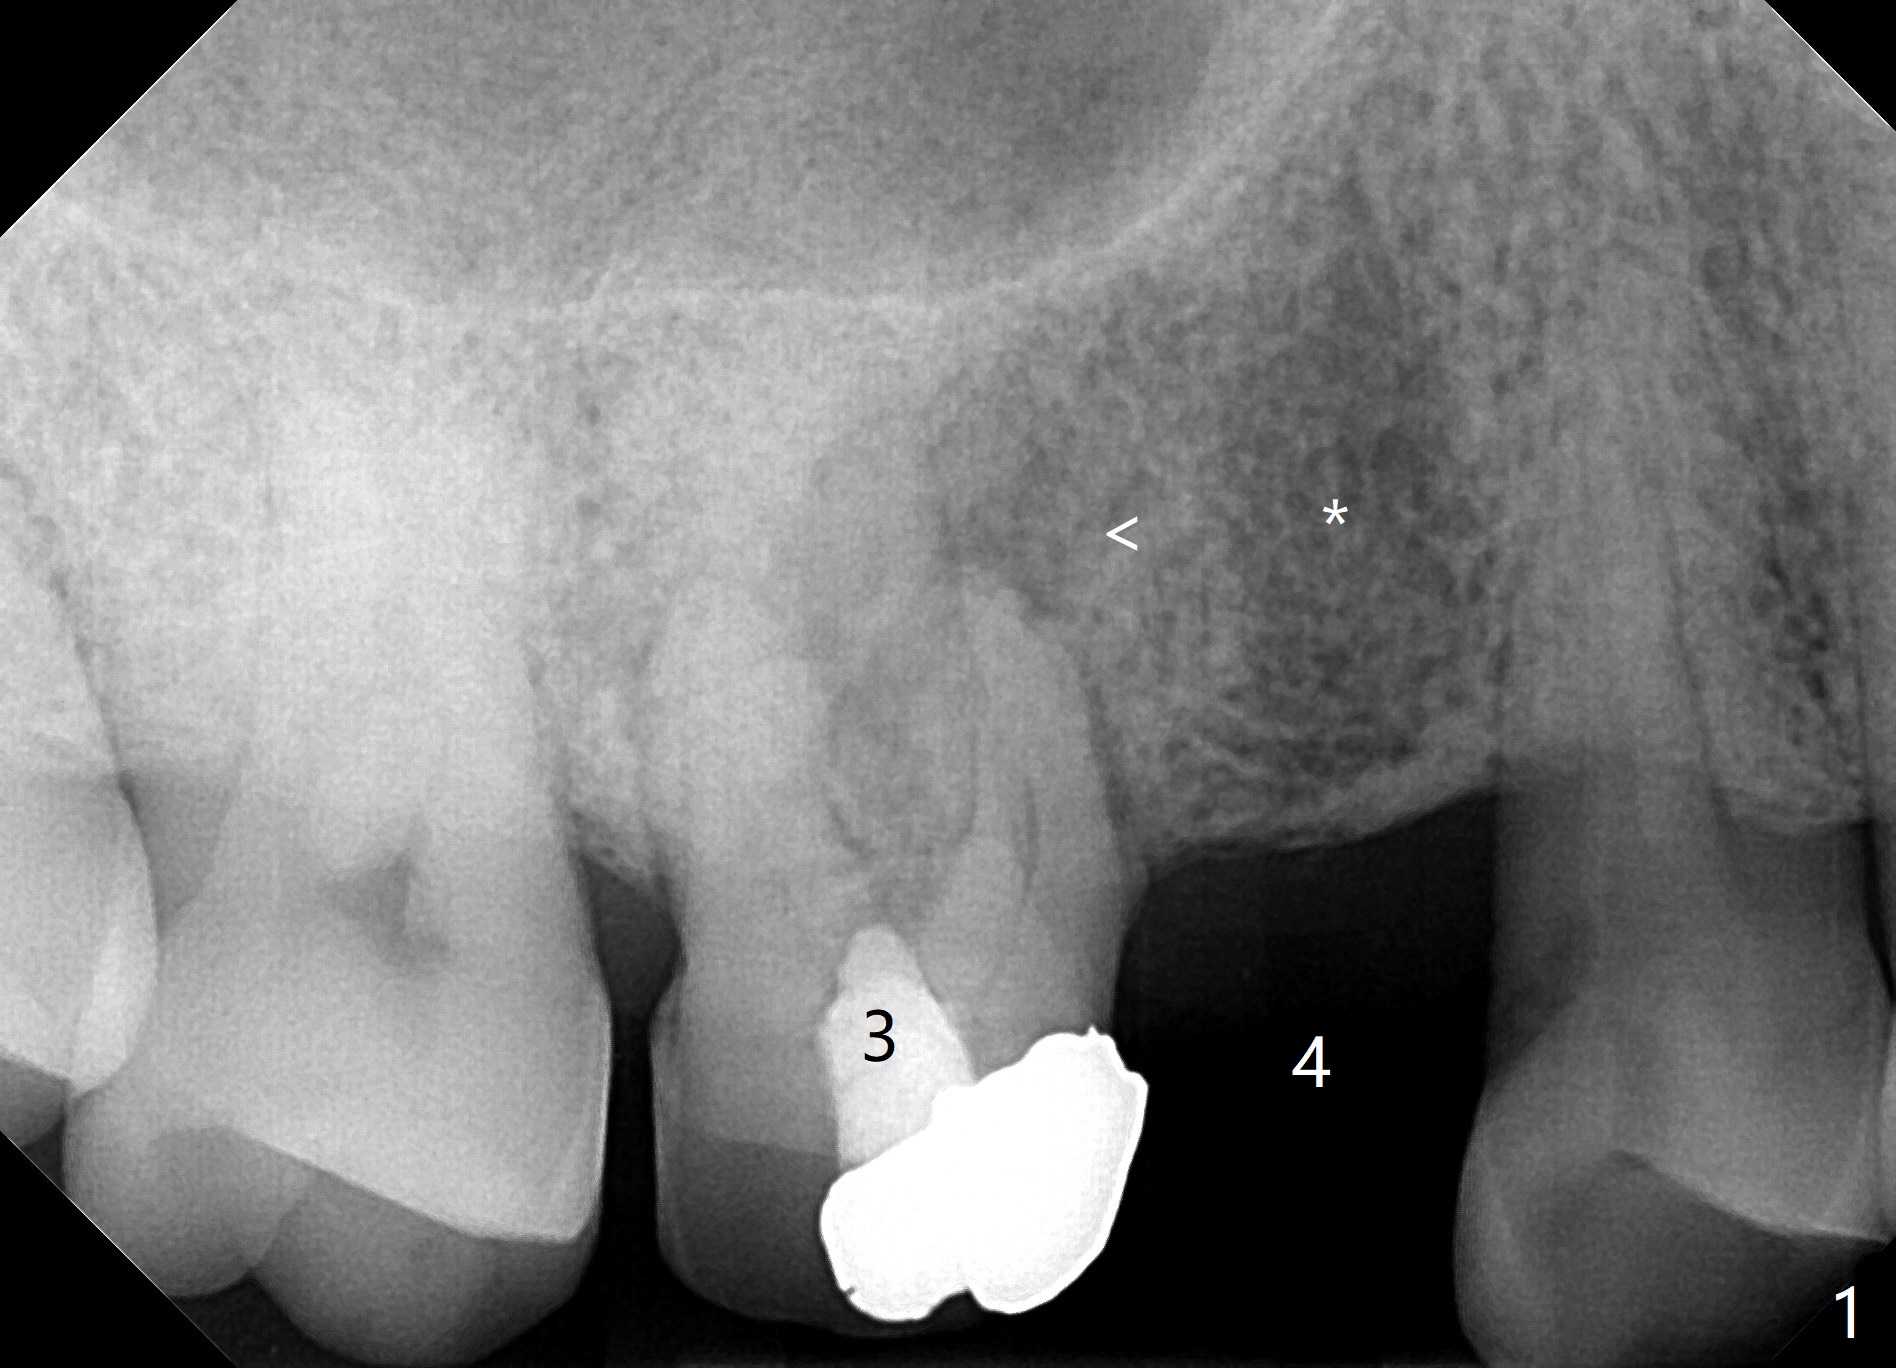

A 67-year-old man used to have a 3/4 cantilever bridge, which is dislodged (Fig.1). The anchor tooth has a buccal fistula with apparent furca perforation and mesiobuccal periapical radiolucency (<). Prior to extraction, the tooth will be used as a surgical guide for implant placement at #4 (Fig.2). Since the bone density at #4 seems to be low (*), bone expander kit will be used.